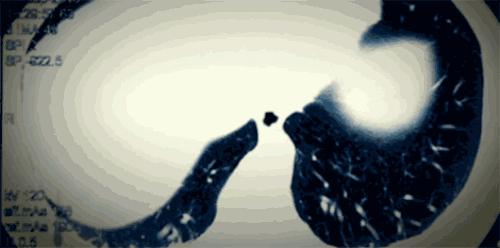

爷爷在我大一那年确诊为膀胱癌,140的体重瞬间打了个对折,掉到70多斤。整个人瘦削得只剩一副骨架,眼睛也因视觉神经受到压迫而失了明。

她在上海工作,去年10月份被查出患有“滤泡型淋巴瘤2级”。

这是一种非常严重、非常罕见的癌症。短短21天内,她就经历了口腔粘膜脱落、发烧脾虚、浮肿剧痛、手和脸失去知觉等常人不曾体会的痛苦。

发现癌症的契机,是一次普通的公司体检。当医生触碰到她的甲状腺结节时,发现了异常肿大的淋巴结。一切来得那么突然,又那么顺理成章。

这不是个例。去年7月,30多岁的律师小张,胃痛到吐血。到医院检查才发现,已经是胃癌晚期了。按医生的话来说,就是“胃里一片稀烂,手术都难做”,从确诊癌症到去世,不到3个月。